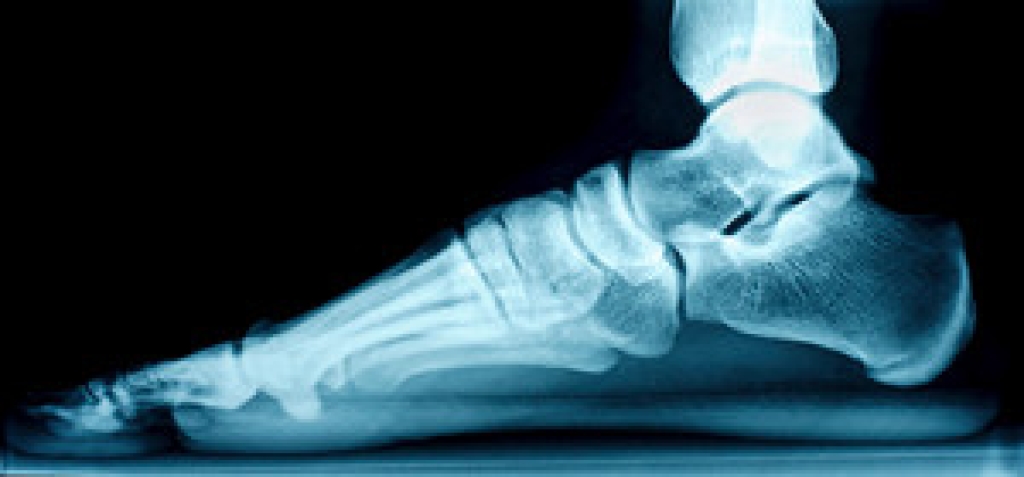

Standing on your feet for long periods of time can cause stress and pain in your feet. Your whole body may experience change in terms of posture, back pain, bunions, callouses and or plantar warts. There are ways to avoid these conditions with proper foot care, smart choices and correct posture.